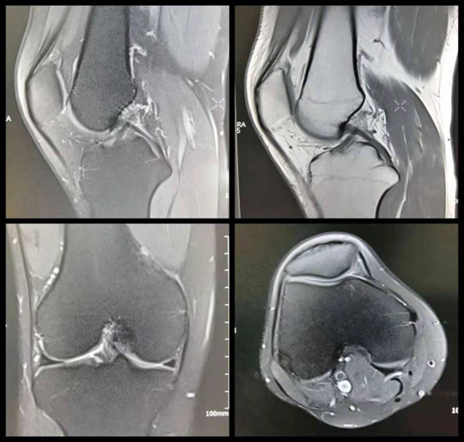

适应症:适用于软组织损伤(如韧带、肌肉、半月板)、骨髓病变、神经病变、关节炎等。

优势:无需辐射,对软组织的显像能力极强,可清晰显示内部结构和病变。

局限性:检查时间较长,不适用于急危重病人、婴幼儿及欠配合的老年人,体内有金属植入物、起搏器、义齿等磁性物质为检查禁忌症。其次检查成本高,对钙化灶和空气的显像不如CT。